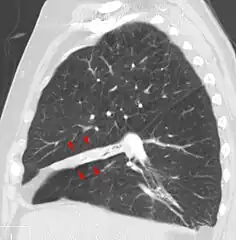

Atelectasis.

Clinically significant atelectasis is generally visible on chest X-ray; findings can include lung opacification and/or loss of lung volume. Post-surgical atelectasis will be bibasal in pattern. Chest CT or bronchoscopy may be necessary if the cause of atelectasis is not clinically apparent. Direct signs of atelectasis include displacement of interlobar fissures and mobile structures within the thorax, overinflation of the unaffected ipsilateral lobe or contralateral lung, and opacification of the collapsed lobe. In addition to clinically significant findings on chest X-rays, patients may present with indirect signs and symptoms such as elevation of the diaphragm, shifting of the trachea, heart and mediastinum; displacement of the hilus and shifting granulomas.[10]